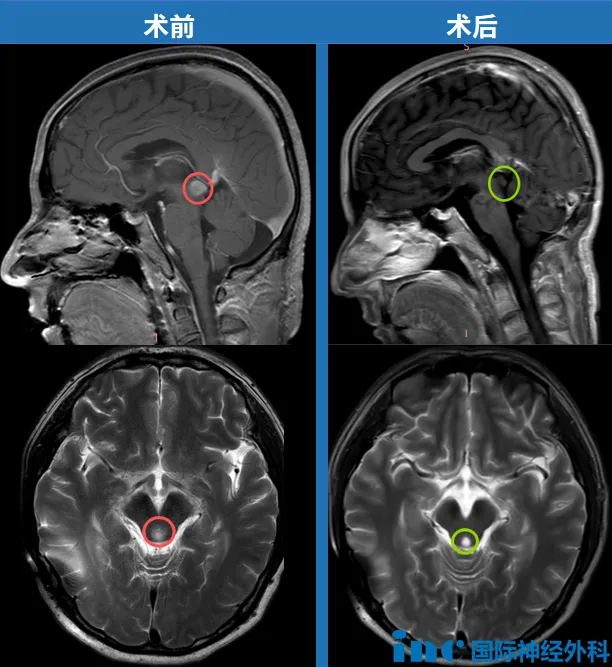

谁按下了快进键?让这个胶质瘤快速蔓延? 年过半百的李先生出现腿部发麻,腰痛,无法行走。经在当地医院检查后诊断为延髓肿瘤,医生认为这个位置手术风险太大,不建议手术。不到一个...

脑干延髓,位于大脑核心区,其内含有呼吸、心跳、意识觉醒、吞咽等基本生命活动中枢,是维持生命关键的神经结构,含有全部的神经传导通路。 历年来,包括延髓在内的整个脑干区域一直...